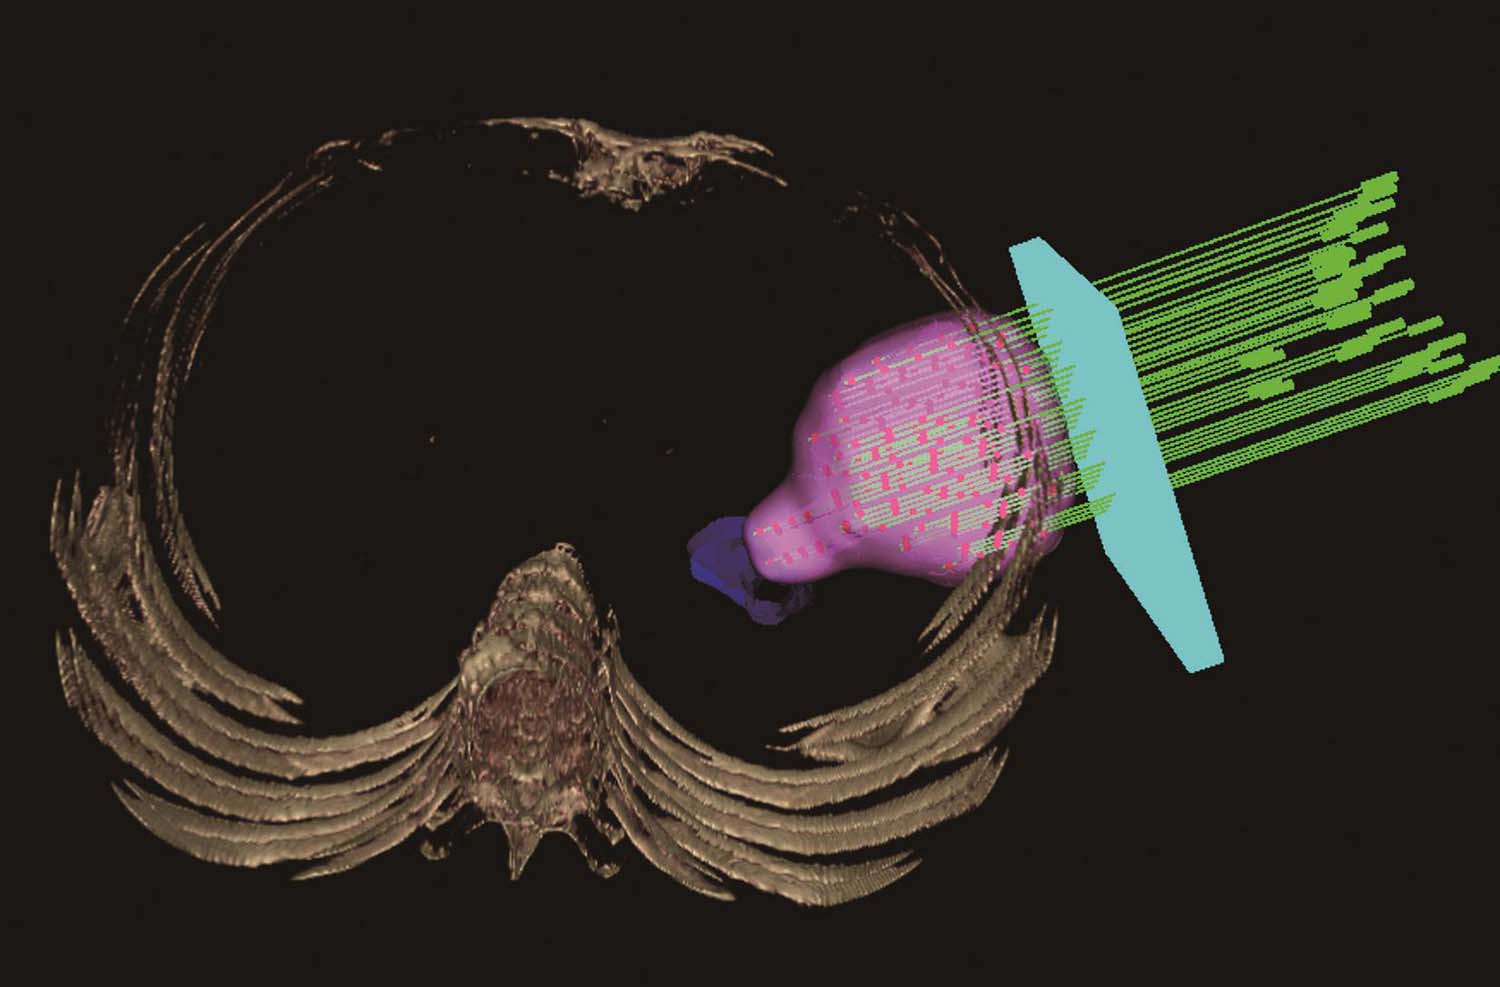

2)三维重建皮肤、骨骼、靶区及危及器官(图4-4-3):大体观察可能的进针路径,首先看是否肿瘤的各部位均可用共面针道穿刺到位,如果不能完全用共面针道解决,则观察可行的非共面针道进针路径。

图4-4-3 三维重建皮肤、靶区及危及器官

术前手术体位真空垫固定患者,行CT扫描,勾画靶区及危及器官,三维重建,查看靶区与危及器官的解剖关系(图4-4-6)。根据医师给定的处方剂量及粒子活度设计进针路径及粒子分布,计算等剂量分布,得出术前DVH图。计划审核无误后将数据传送至3D打印机打印模板。

术中根据术前计划体位摆放患者手术体位,采用负压真空垫固定,消毒铺巾后再次激光线定位患者。患者位置无误后将模板放置于患者体表,激光线校准模板位置。然后在预设的定位针道内穿刺定位针,激光线校准位置。定位针穿刺到位后扫描CT,观察定位针实际位置与术前计划一致后穿刺其他植入针,所有植入针到位后扫描CT,确认植入针实际针道与术前计划是否一致,如果不一致,可在相应辅助孔重新穿刺。所有针道位置无误后按照术前计划植入粒子。粒子植入完毕后扫描CT,比较实际粒子位置与计划位置是否一致,如有剂量不足区域及时补植。(图4-4-7)

图4-4-6 三维重建查看靶区与危及器官的解剖关系

图4-4-7 模板位置无误后在模板引导下一次性穿刺所有穿刺针